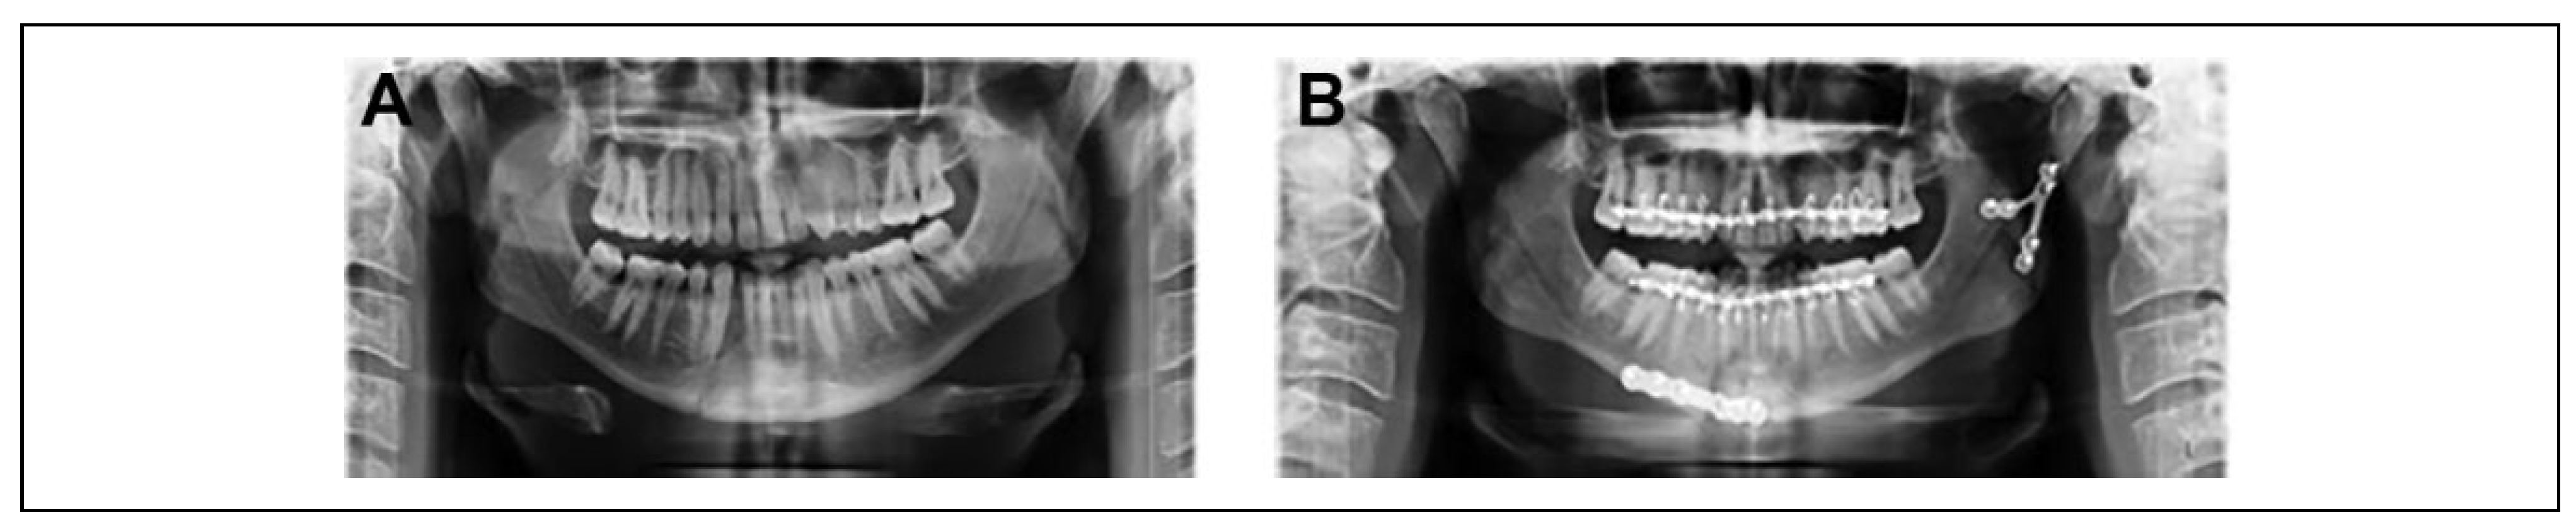

Surgical Procedure

- Olivier T, Pierre T, Gabriel M. Open reduction internal fixa- tion of low subcondylar fractures of mandible through high cervical transmasseteric anteroparotid approach. J Oral Max- illofac Surg, 2446.

- Narayanan V, Ramadorai A, Ravi P, Nirvikalpa N. Transmas- seteric anterior parotid approach for condylar fractures: expe- rience of 129 cases. Br J Oral Maxillofac Surg. [CrossRef] [PubMed]